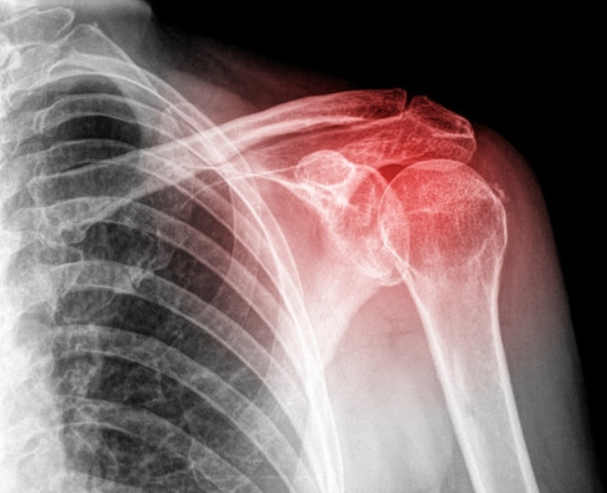

▣ 어깨는뼈는 크게 3가지입니다.

어깨 상완골(긴팔뼈)

쇄골

견갑골

▣ 석회 성 건염

석회 성 건염의 원인을 확인할 수는 없지만 상당히 고통스러울 수 있습니다. 칼슘 침착 물이 근육이나 힘줄에 축적되는 상태로 석회 성 건염을 설명합니다. X- 레이로 볼 수 있으며 일반적으로 30세 이상이지만 모든 연령에서 발생할 수 있는 사람들에게 더 흔합니다.